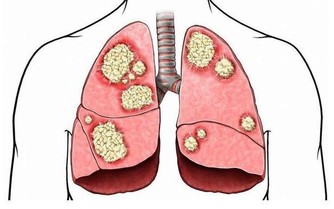

(3)患有腎臟疾病的人群

五穀雜糧的蛋白質、鉀、磷含量偏高,如果當成主食食用,有可能會加重腎臟負擔,從而嚴重影響人體健康,因此患有腎臟疾病的患者,日常飲食中要注意少吃五穀雜糧類食物。